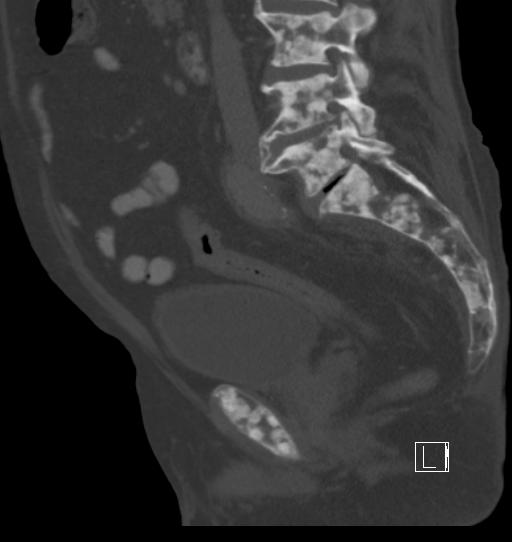

- Diffuse skeletal

- Oncohaematology